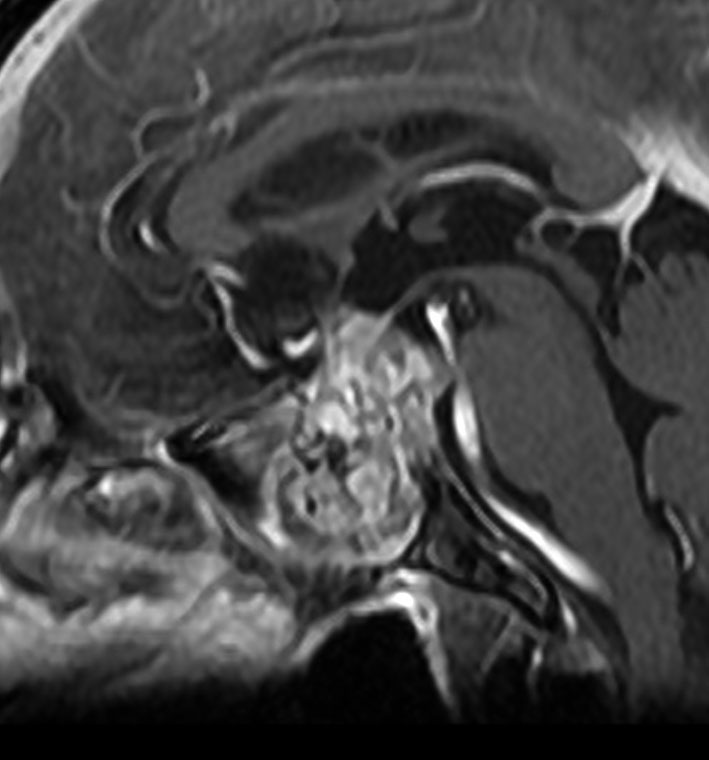

MRI T2強調画像(左)では等信号から高信号のまだらな境界が不明瞭な腫瘍が斜台から左海綿静脈洞内に浸潤しているのがみられます。T1強調ガドリニウム増強では,腫瘍がまだらに増強されています。トルコ鞍から鞍上部に伸び,視交差を侵し第3脳室底まで伸展しています。脊索腫が硬膜内に浸潤して神経組織と癒着することは珍しいことではありません。